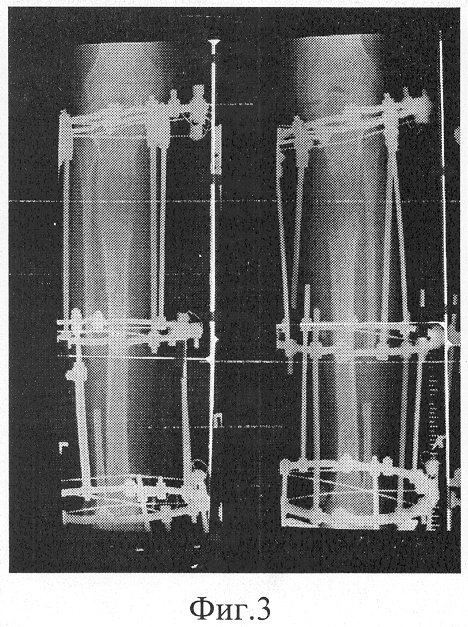

фиг.3 – фоторентгенограмма голеней больного в процессе дистракции;

В послеоперационном периоде, начиная с 4-го дня после операции, осуществляли дозированную продольную дистракцию фрагментов со средним темпом 0,5-1,0 мм в сутки. При этом выделенные дистальные фрагменты берцовых костей перемещали по спиралеобразной траектории с частичным на 5-10° отклонением от продольной оси. Указанное перемещение производили путем поочередного, последовательного создания тракционных усилий по стержням, соединяющим опоры со спицами, фиксирующими проксимальные и дистальные фрагменты берцовых костей. Общая продолжительность тракции указанным выше способом составила 92 дня.

На контрольных рентгенограммах, выполняемых в течение всего срока дистракции, а также в ходе последующего периода фиксации продолжительностью 84 дня, отмечалось равномерное по всей площади контакта с материнскими отломками формирование дистракционного костного регенерата. Его диаметр в средней части превышал в среднем на 1-2 мм с каждой из сторон диаметр материнской кости, а оптическая плотность, за исключением зоны активного остеогенеза, приближалась к оптической плотности прилежащих участков кости.